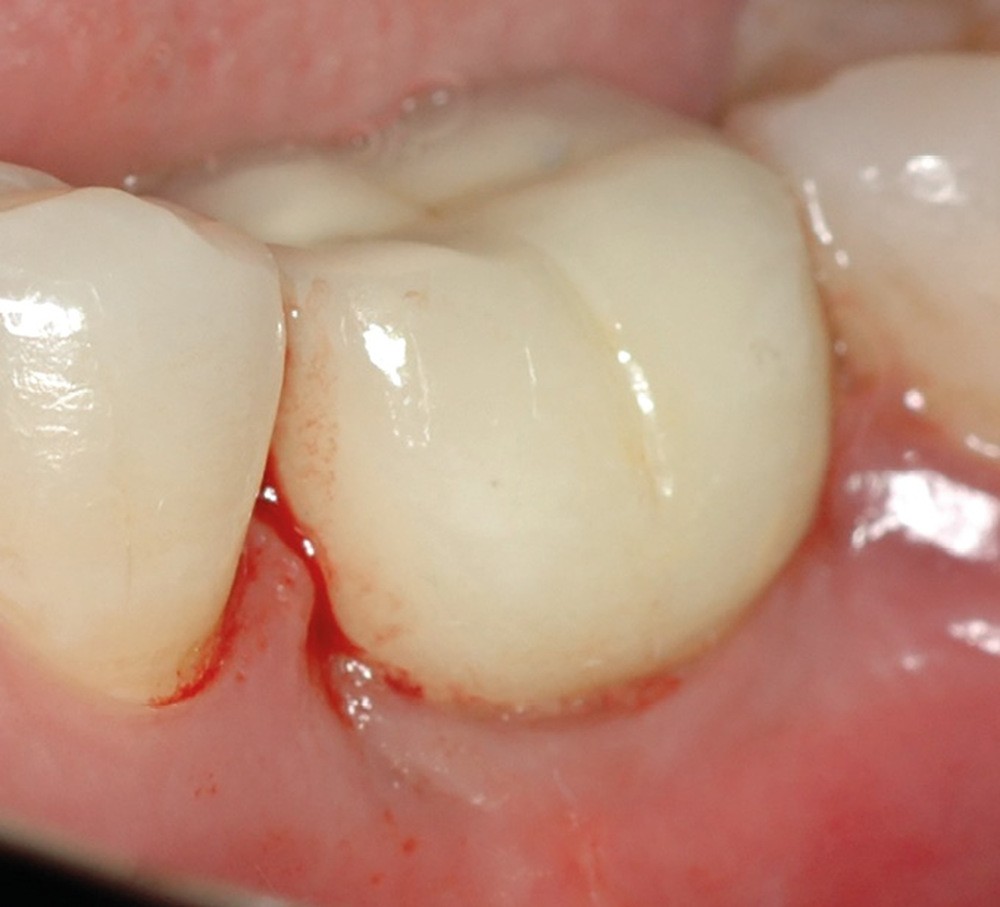

- Péri-implantite diagnostiquée en 2021